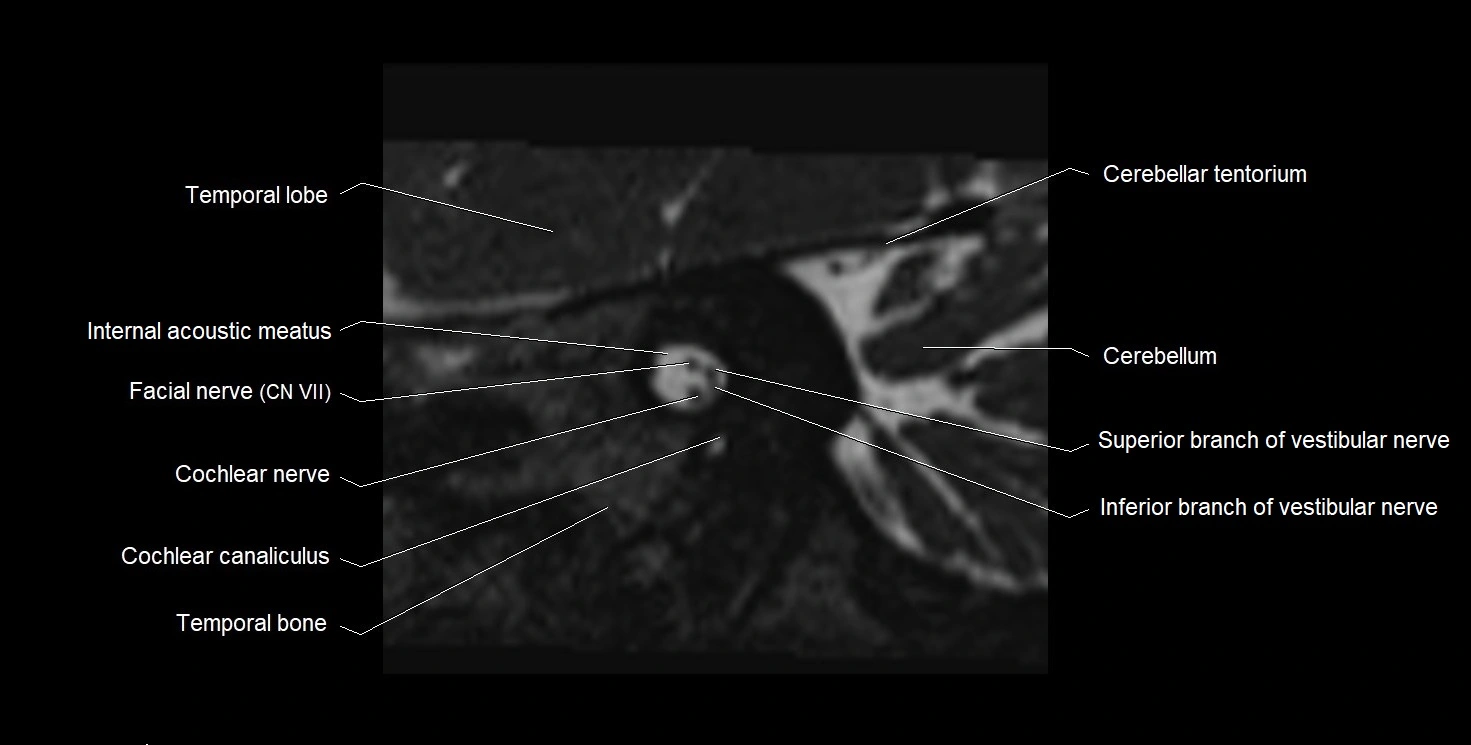

MRI images

image